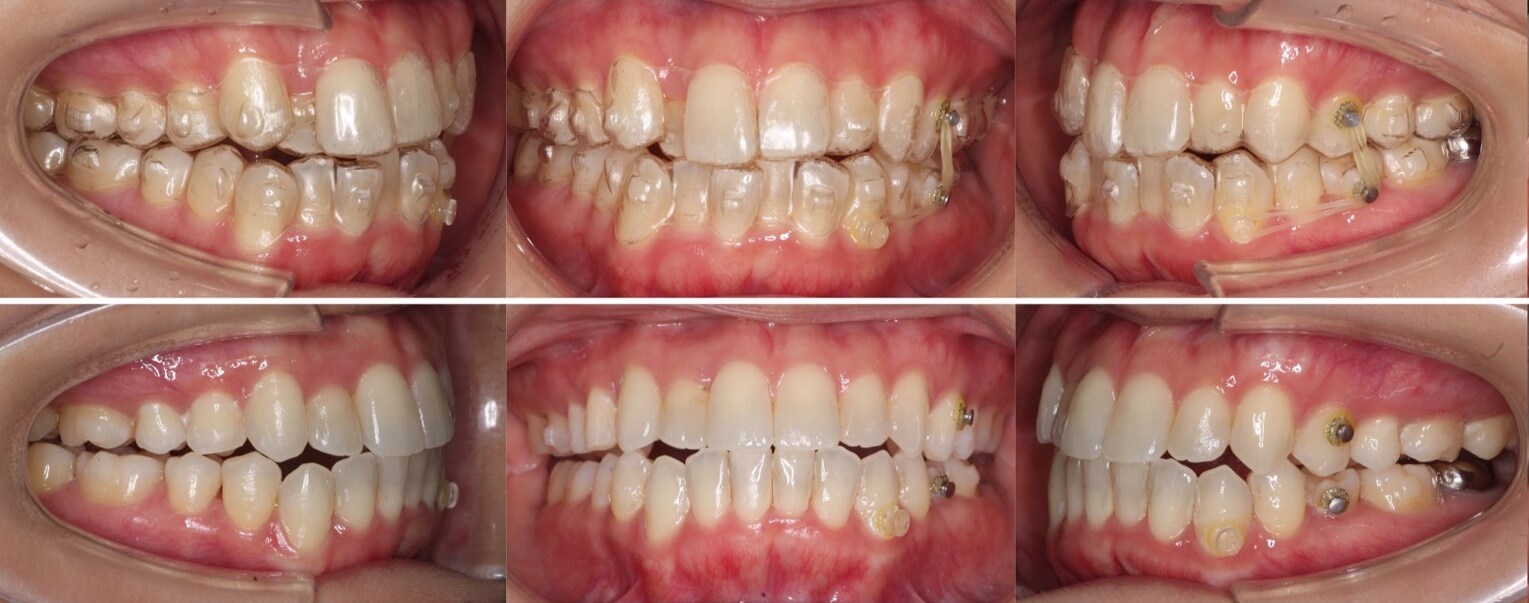

46歳女性・唇側矯正装置・抜歯

<症例概要>

主訴:前歯と口元の突出

年齢・性別:43歳女性

住まい:千葉県佐倉市

症状:叢生・上下顎前歯唇側傾斜

治療方針:上左右5番・下左右4番(計4本)

治療装置:唇側矯正装置

固定装置:ナンスホールディングアーチ

治療期間:3年

リテーナー:下フィックス+上下クリアタイプ

治療費用:968,000(税込)

代表的副作用:痛み・治療後の後戻り・歯根吸収・歯髄壊死・歯肉退縮

▶︎その他の副作用

前歯の突出のため口が閉じづらいことを気にされていて矯正治療を希望された患者さんです。年齢的に抜歯を行うか迷ったのですが、患者さんの主訴を優先して抜歯矯正により前歯を後方移動させました。抜歯部位については、上の歯並びは治療歯である第二小臼歯(5番)を選択しています。その分、治療期間は3年を超えてしまったのですが、理想的な横顔になりました。